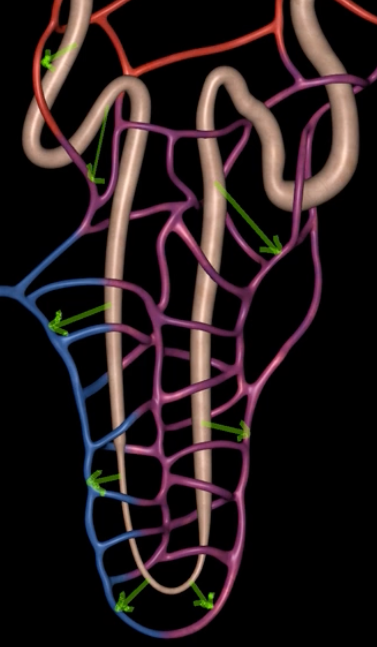

afferent arteriole

yellow

glomerulus

green

efferent arteriole

purple

orange: peritubular capillaries

green: vasa recta

efferent arteriole give rise to orange and green

yellow: cortical nephron

blue: juxtamedullary nephron

yellow:

blue: